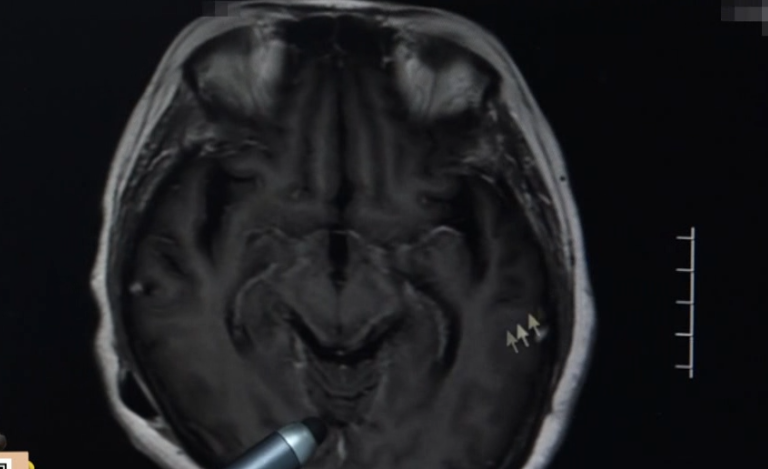

原来,陈阿姨是颅内感染了

李斯特菌

广东三九脑科医院神经内二科主任 钟水生:当时发现她颅压非常高,里面有炎症,而且在脑积液和血里面都培养出了李斯特菌。